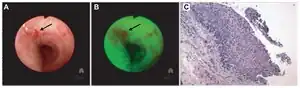

Una condición precancerosa es una condición o lesión que involucra células anormales que se asocian con un mayor riesgo de desarrollar cáncer.[1][2][3] Clínicamente, las condiciones precancerosas abarcan una variedad de afecciones o lesiones con un mayor riesgo de desarrollar cáncer. Algunas de las afecciones precancerosas más comunes incluyen ciertos pólipos de colon, que pueden progresar a cáncer de colon, gammapatía monoclonal de importancia indeterminada, que puede progresar a mieloma múltiple o síndrome mielodisplásico,[4] displasia cervical, que puede progresar a cáncer cervical,[5] y el "carcinoma in situ de pulmón (CIS)" precursor preinvasivo del carcinoma epidermoide pulmonar de células escamosas.[6][7]

Patológicamente, las lesiones precancerosas pueden variar desde neoplasias benignas, que son tumores que no invaden los tejidos normales adyacentes y no se diseminan a órganos distantes, hasta la displasia,[1] que involucra un agrupamiento de células anormales, que en algunos casos tienen un mayor riesgo de progresar a anaplasia y cáncer invasivo. A veces se usa el término "precáncer" para el carcinoma in situ, que es un cáncer no invasivo que no ha progresado a una etapa agresiva e invasiva. Al igual que con otras afecciones precancerosas, no todos los carcinomas in situ progresarán a una enfermedad invasiva.[6]